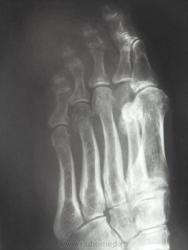

женщина обратилась с жалобами к участковому терапевту на боли во 2 и 3 пальцах правой стопы, предварительный диагноз у них как всегда " артроз", про травму ничего не пишут в амбулаторной карте, как внешне выглядит стопа тоже не описывают. Может ли это быть патологическим переломом????

Перелом по типу маршевого, но так как на фоне минералопении - это ближе к Лоозера, чем Дойчлендера...

Боюсь прослыть упрямым ... Но все-таки... Дружный DS б-ни Дойчлендера выставлен только на основании утверждения, что травмы не было. Я тут "посоветовался" с С.А.Рейнбергом. Он утверждает, что отличительной особенностью полоски просветления при б.Д. является ее ровность, прямолинейность. При переломах полоска зигзагообразная, что мы и имеем. На фоне остеопении больная могла просто наступить на камень и этого не заметить. Вот вам и перелом.

Патологическая перестройка от перенапряжения может возникать в разных костях, однако наиболее типичные места – дистальный отдел 2-й или 3-й (реже) плюсневых костей и проксимальный метафиз большой берцовой кости. Первая локализация носит название в литературе как «маршевая стопа», перелом Дойчлендера, усталостная стопа и др. и встречается чаще у солдат-новобранцев. Перестройка большой берцовой кости встречается чаще у спортсменов в период интенсивных тренировок.

На рентгенограммах выявляется локальная периостальная реакция в виде одно- или многослойного периостоза. Соответственно ему в костномозговом канале появляется склероз, сужающий просвет канала. В кортикальном слое и среди склероза видна полоска просветления, чаще имеющая клиновидную форму- собственно « ползучий » перелом. При продолжении действии нагрузки он постепенно увеличивается. Однако если травмирующий фактор прекращает свое действие, достаточно быстро восстанавливается нормальная структура кости.

Описанная перестройка костной ткани возникает у практически здоровых людей при чрезмерно высоких, длительных переменных нагрузках. Однако аналогичная анатомо-функциональное несоответствие может возникнуть и при обычных нагрузках, характерных для повседневной бытовой и профессиональной деятельности у больных с некоторыми заболеваниями, сказывающимися на состоянии костной ткани: это фиброзная дисплазия, эндокринопатии, болезнь Педжета, рахитоподобные заболевания. У пациентов при этих заболеваниях ухудшаются механические свойства костной ткани, и при длительных, хотя и не очень высоких нагрузках возникает патологическая перестройка в метафизах длинных костей, лонной и седалищной костях, шейки бедренной кости, ребрах. Рентгенологическая картина такого «ползучего» перелома наслаивается на картину основного заболевания. Перестроичные переломы возникают на вершине искривления кости при ее дугообразной деформации. Эти зоны перестройки впервые описаны Лоозером и носит название лоозеровских зон просветления.